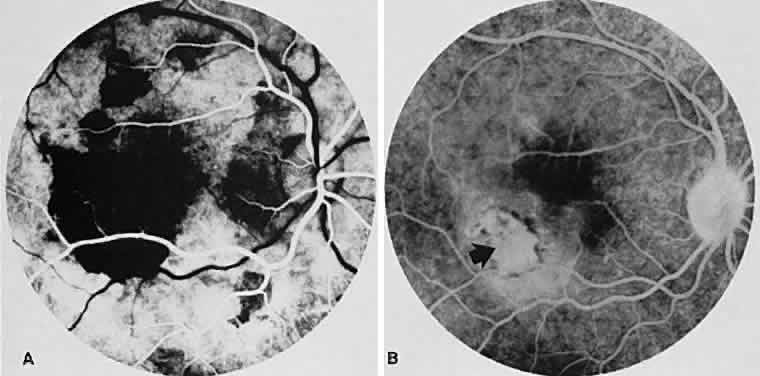

Fig. 15. Subretinal neovascularization in serpiginous choroiditis. A. The arteriolar phase of the angiogram of the right eye shows a geographic center of choroidal hypofluorescence in the macula. There are additional areas of hypofluorescence superior to the right macular region. B. The venous phase of the angiogram shows a subretinal neovascular membrane just inferior and temporal to the macular zone (arrow). The hypofluorescence has decreased markedly in size compared with (A). The marked hypofluorescence masked the subretinal neovascular membrane initially.

Fluorescein angiography of the acute lesions shows early hypofluorescence due to blockage of the underlying choroidal fluorescence with eventual hyperfluorescent staining of the lesions' margins (see Fig. 14B and C). Later, there is patchy hyperfluorescence of the lesion due to leakage from the lesions' margins and from islands of normal choroid and choriocapillaris within the lesion. Sometimes the lesion becomes indistinguishable from the surrounding background fluorescence of the normal retina.46–48 The old lesions are hypofluorescent and are bordered by hyperfluorescence from the adjacent normal choriocapillaris. Hyperfluorescence of the old lesions occurs because of scar tissue that stains in the late phase of fluorescein angiography.

SRNV is a well-known complication of serpiginous choroidopathy. Occasionally, ophthalmoscopic signs such as subretinal blood and exudate can be seen. However, SRNV often appears like recurrent serpiginous lesions and can be diagnosed in patients only by fluorescein angiography, with persistent late enlarging hyperfluorescence of the lesions (see Fig. 15).49 The differential diagnosis includes AMPPPE, age-related macular degeneration, presumed ocular histoplasmosis, and choroidal ischemia.

In the acute stage, ICG angiography shows diffuse, homogeneous, marked, and persistent hypofluorescence during all phases of the angiogram in areas of active inflammation. Active choroidal involvement beyond the boundaries observed by ophthalmoscopy as well as those delineated by FA is noted. In the subacute phase of the disease, heterogeneous hypofluorescence with clear visualization of medium and large choroidal vessels is seen. In the healed stages, delayed or absent choroidal filling in the early transit phase with better visualization of deeper choroidal vessels because of loss of overlying RPE and inner choroid may be shown. If SRNV develops, hyperfluorescence of the lesion is noted.50,51